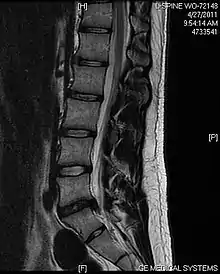

L'imagerie par résonance magnétique peut montrer la hernie, le canal vertébral, les nerfs, les tissus environnants. Les tissus mous sont les mieux analysés par cet examen qui est le plus performant pour le diagnostic de hernie discale. Les images pondérées en T2 montrent clairement la hernie.

IRM cervicale sagittale montrant une hernie discale de niveau C5-C6.